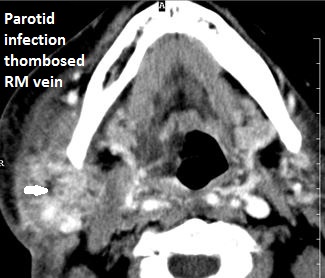

The retromandibular and the facial veins are abnormal.

There is evidence of thrombus, thrombophlebitis or other occlusive or inflammatory process of the jugular vein or smaller venous tributaries.